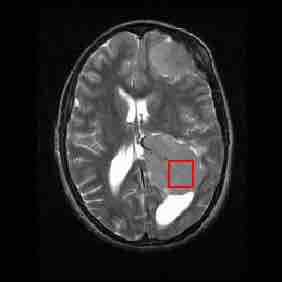

MRI brain scan (in the axial plane—that is, slicing from front-to-back and side-to-side through the head) showing a brain tumor at the bottom right.